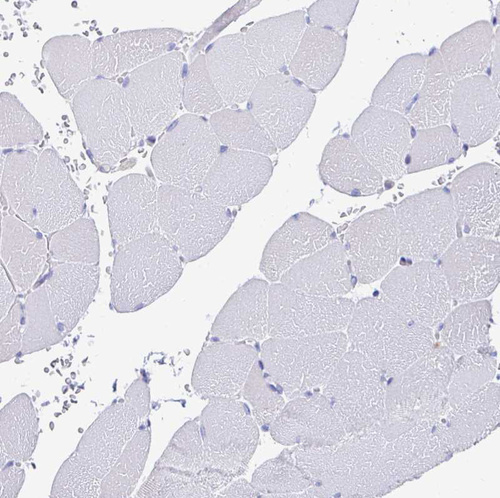

Immunohistochemistry analysis in human placenta and skeletal muscle tissues using HPA022814 antibody. Corresponding LAMC3 RNA-seq data are presented for the same tissues.